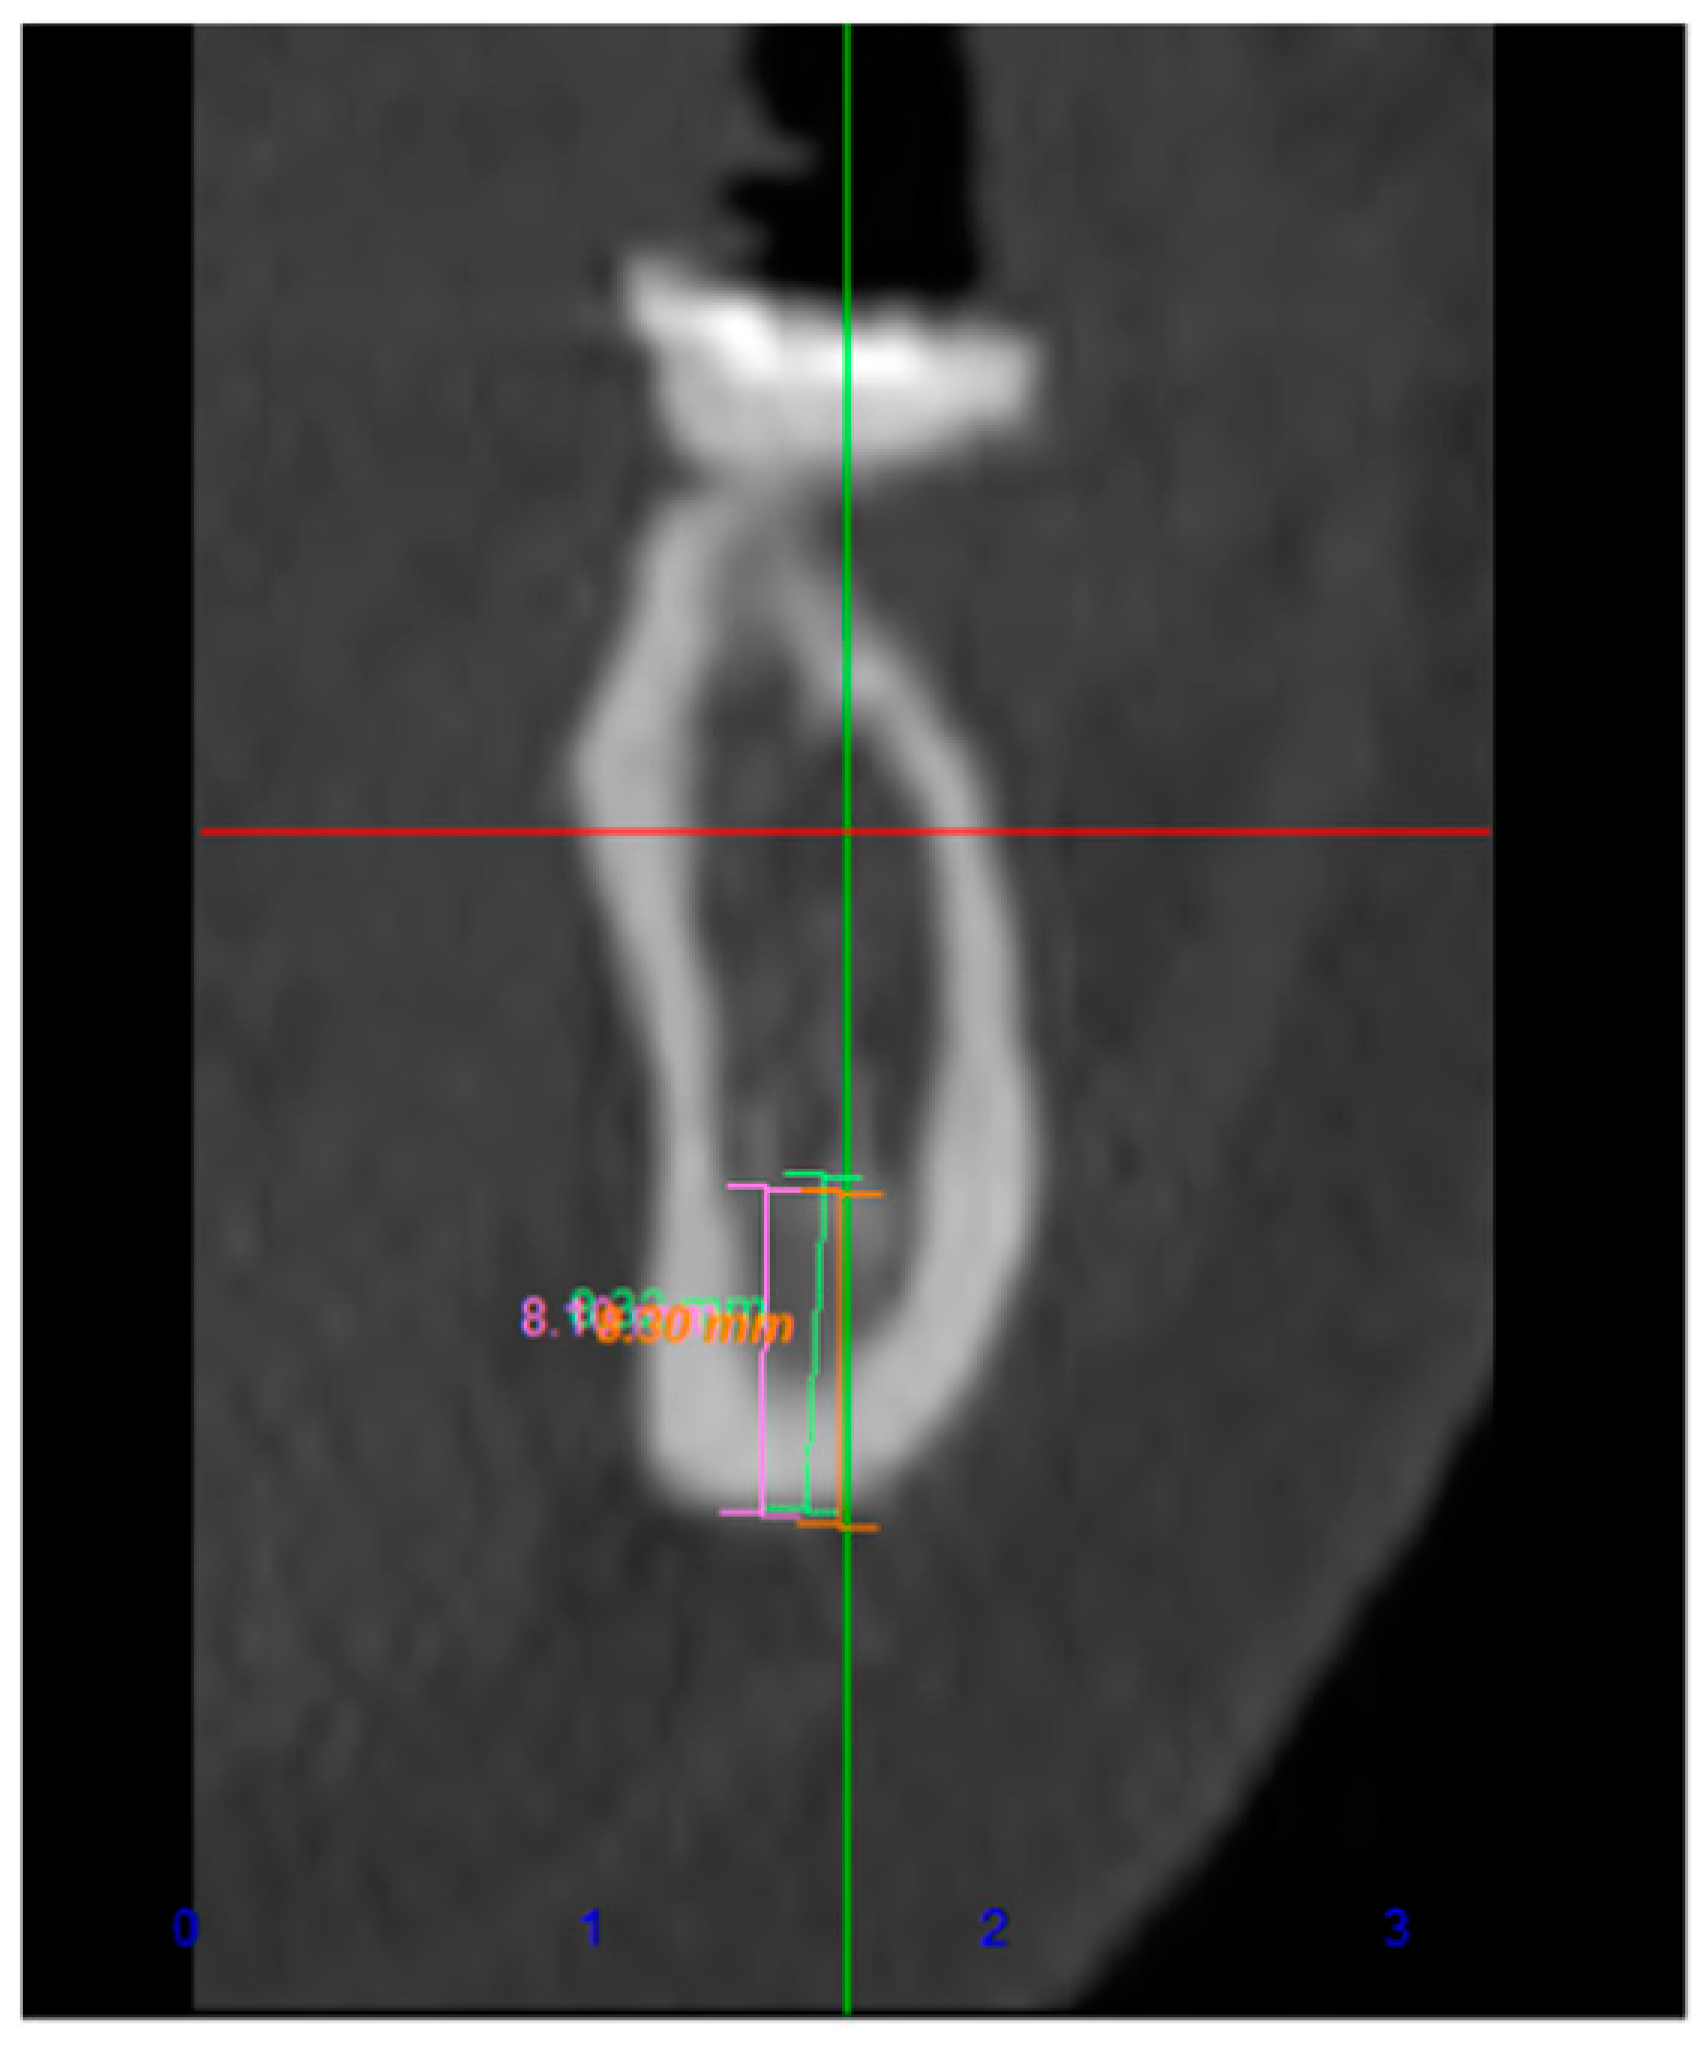

Tomographic Evaluation of Bone Height Between the Mandibular Canal and the Inferior Cortex of the Mandible Related to Bicortical Screws Fixation

Fares, R.D.; Leal, J.V.B.; da Silva Areas, M.Z.; da Rocha, H.V.; de Moraes, S.L.C.; Homsi, N.; da Silva, J.R. Tomographic Evaluation of Bone Height Between the Mandibular Canal and the Inferior Cortex of the Mandible Related to Bicortical Screws Fixation. Craniomaxillofac. Trauma Reconstr. 2024, 17, 181-185. https://doi.org/10.1177/19433875231213892